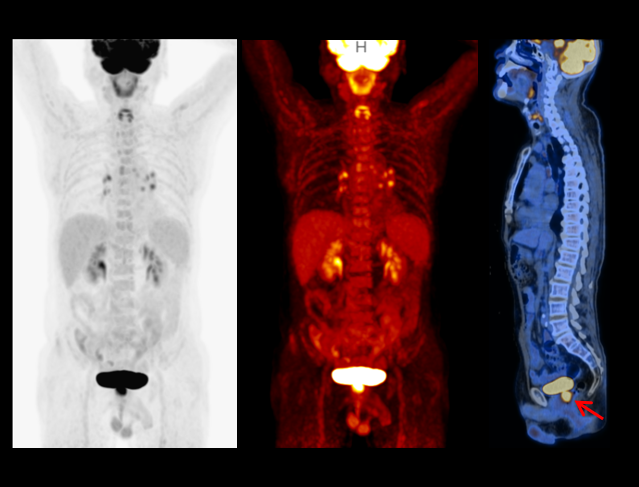

The very fine sampling voxels acquire massive information, bringing exquisite visualization of fine anatomic details.